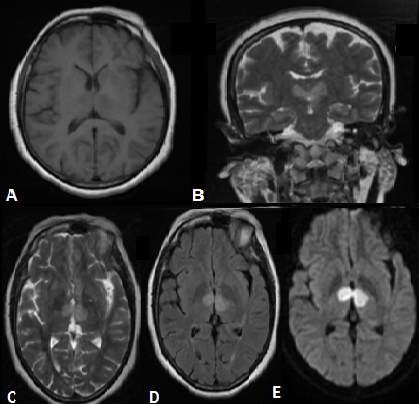

L'infarctus bithalamique par occlusion de l'artère de Percheron est rare et caractérisé par un retard diagnostique. L'IRM cérébrale et un bilan étiologique bien mené permettent de poser le diagnostic et d'adapter le traitement. Cette complication est exceptionnelle au cours du lupus érythémateux systémique. Patiente âgée de 35 ans hospitalisée pour une perte de connaissance d'installation brutale. L'examen physique a objectivé un érythème en vespertilio du visage, une matité de la base pulmonaire droite, un score de Glasgow à 5 et une hémiparésie droite. Les causes toxicologiques, septiques et métaboliques étaient éliminées. L'électrocardiogramme et l'échographie cardiaque était normaux. La TDM cérébrale initiale était sans anomalie. L'IRM cérébrale a montré des anomalies de signal des deux noyaux thalamiques en hyposignal T1, hypersignal T2 et T2 FLAIR avec restriction de la diffusion en rapport avec un accident vasculaire cérébral ischémique récent bithalamique par occlusion de l'artère de Percheron . Le diagnostic de lupus érythémateux systémique associé à un syndrome des antiphospholipides était retenu devant l'association d'un érythème en vespertilio, une pleurésie, une anémie hémolytique auto-immune avec hémoglobine à 9 g/dl, et un bilan immunologique positif avec présence d'anticorps anti-nucléaires et anticorps anti-DNA à un taux élevé, ainsi que des anticardiolipines fortement positifs à 12 semaines d'intervalle. Le traitement s'est basé sur une corticothérapie à forte dose avec dégression progressive des doses et un traitement anticoagulant. L'évolution était marquée par la disparition des signes cliniques et biologiques.